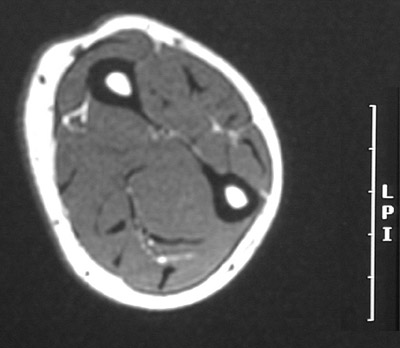

This is a normal axial T1 weighted MRI scan demonstrating the Radius, marrow cavity and Compact or cortical bone and Ulna and Extensor pollicis longus and Extensor carpi ulnaris and Abductor pollicis longus and Extensor digitorum communis and Extensor carpi radialis longus and Brachioradialis and Flexor pollicis longus and Flexor carpi radialis and Tendon of palmaris longus and Flexor digitorum superficialis and Flexor carpi ulnaris and and Flexor digitorum profundus.